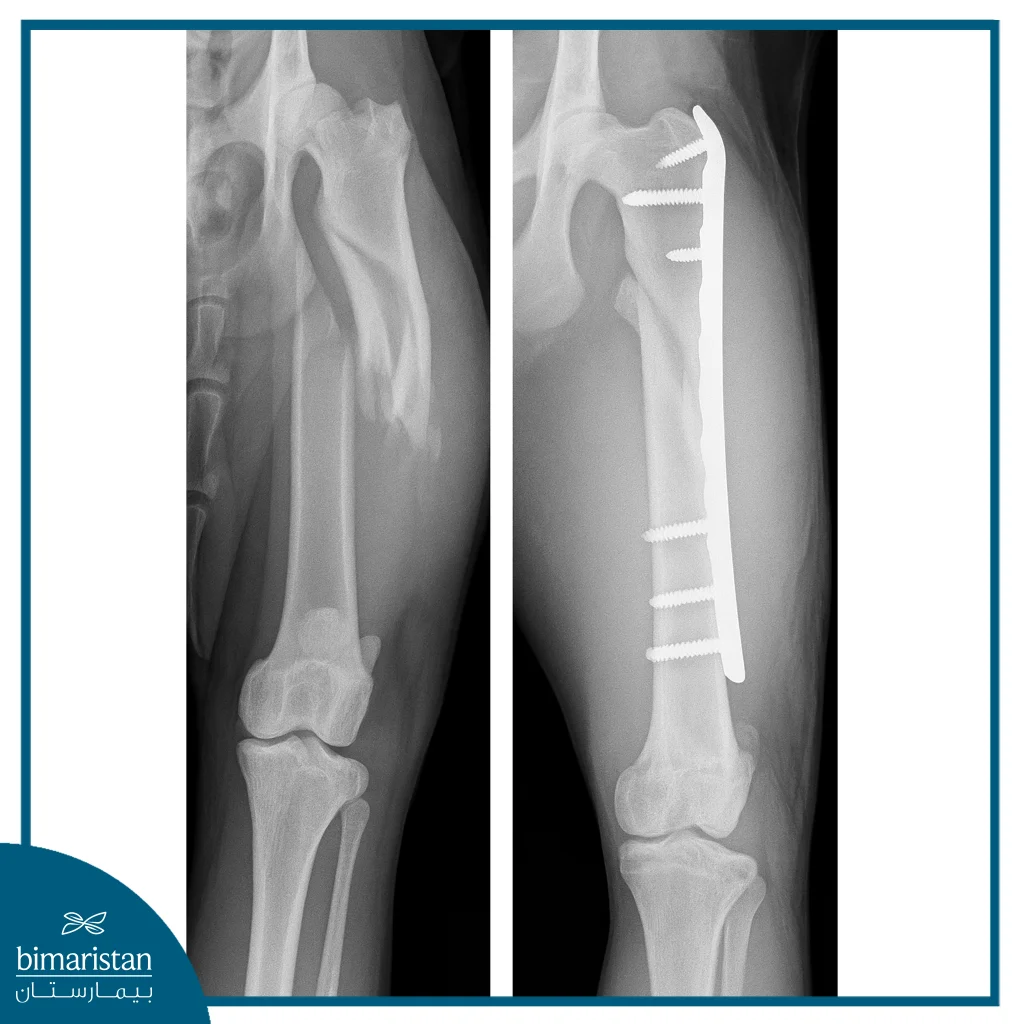

يبدأ التحضير لعملية تثبيت الكسور بالبلاطات الحيوية بمجموعة من الخطوات الدقيقة التي تهدف إلى ضمان نجاح الجراحة وتقليل المضاعفات المحتملة. في البداية، يُجرى تقييم سريري شامل للمريض يتضمن الفحص الجسدي والتصوير الطبي المناسب مثل الأشعة السينية أو التصوير المقطعي (CT)، وذلك لتحديد نمط الكسر، ومكانه، وحجم الشظايا بدقة.

يقوم الطبيب بعد عملية تثبيت الكسور بالبلاطات الحيوية بتصوير شعاعي للتأكد من وضع الصفيحة والبراغي وتقويم الكسر. كما يتم مراقبة المريض وماتبعة علامات العدوى وهل يوجد ألم وكمية البول، والتزام المريض بتعليمات التحميل المحددة من قبل الجراح، في كثير من الحالات يُنصح بتخفيف الوزن/التحميل لفترة محددة. كما يتم متابعة دورية سريرية وتصويرية لمراقبة التئام العظم وفي حالة الصفائح القابلة للتحلل تتم مراقبة مرحلة التحلل وتغيرات القوة الحاملة بمرور الوقت.